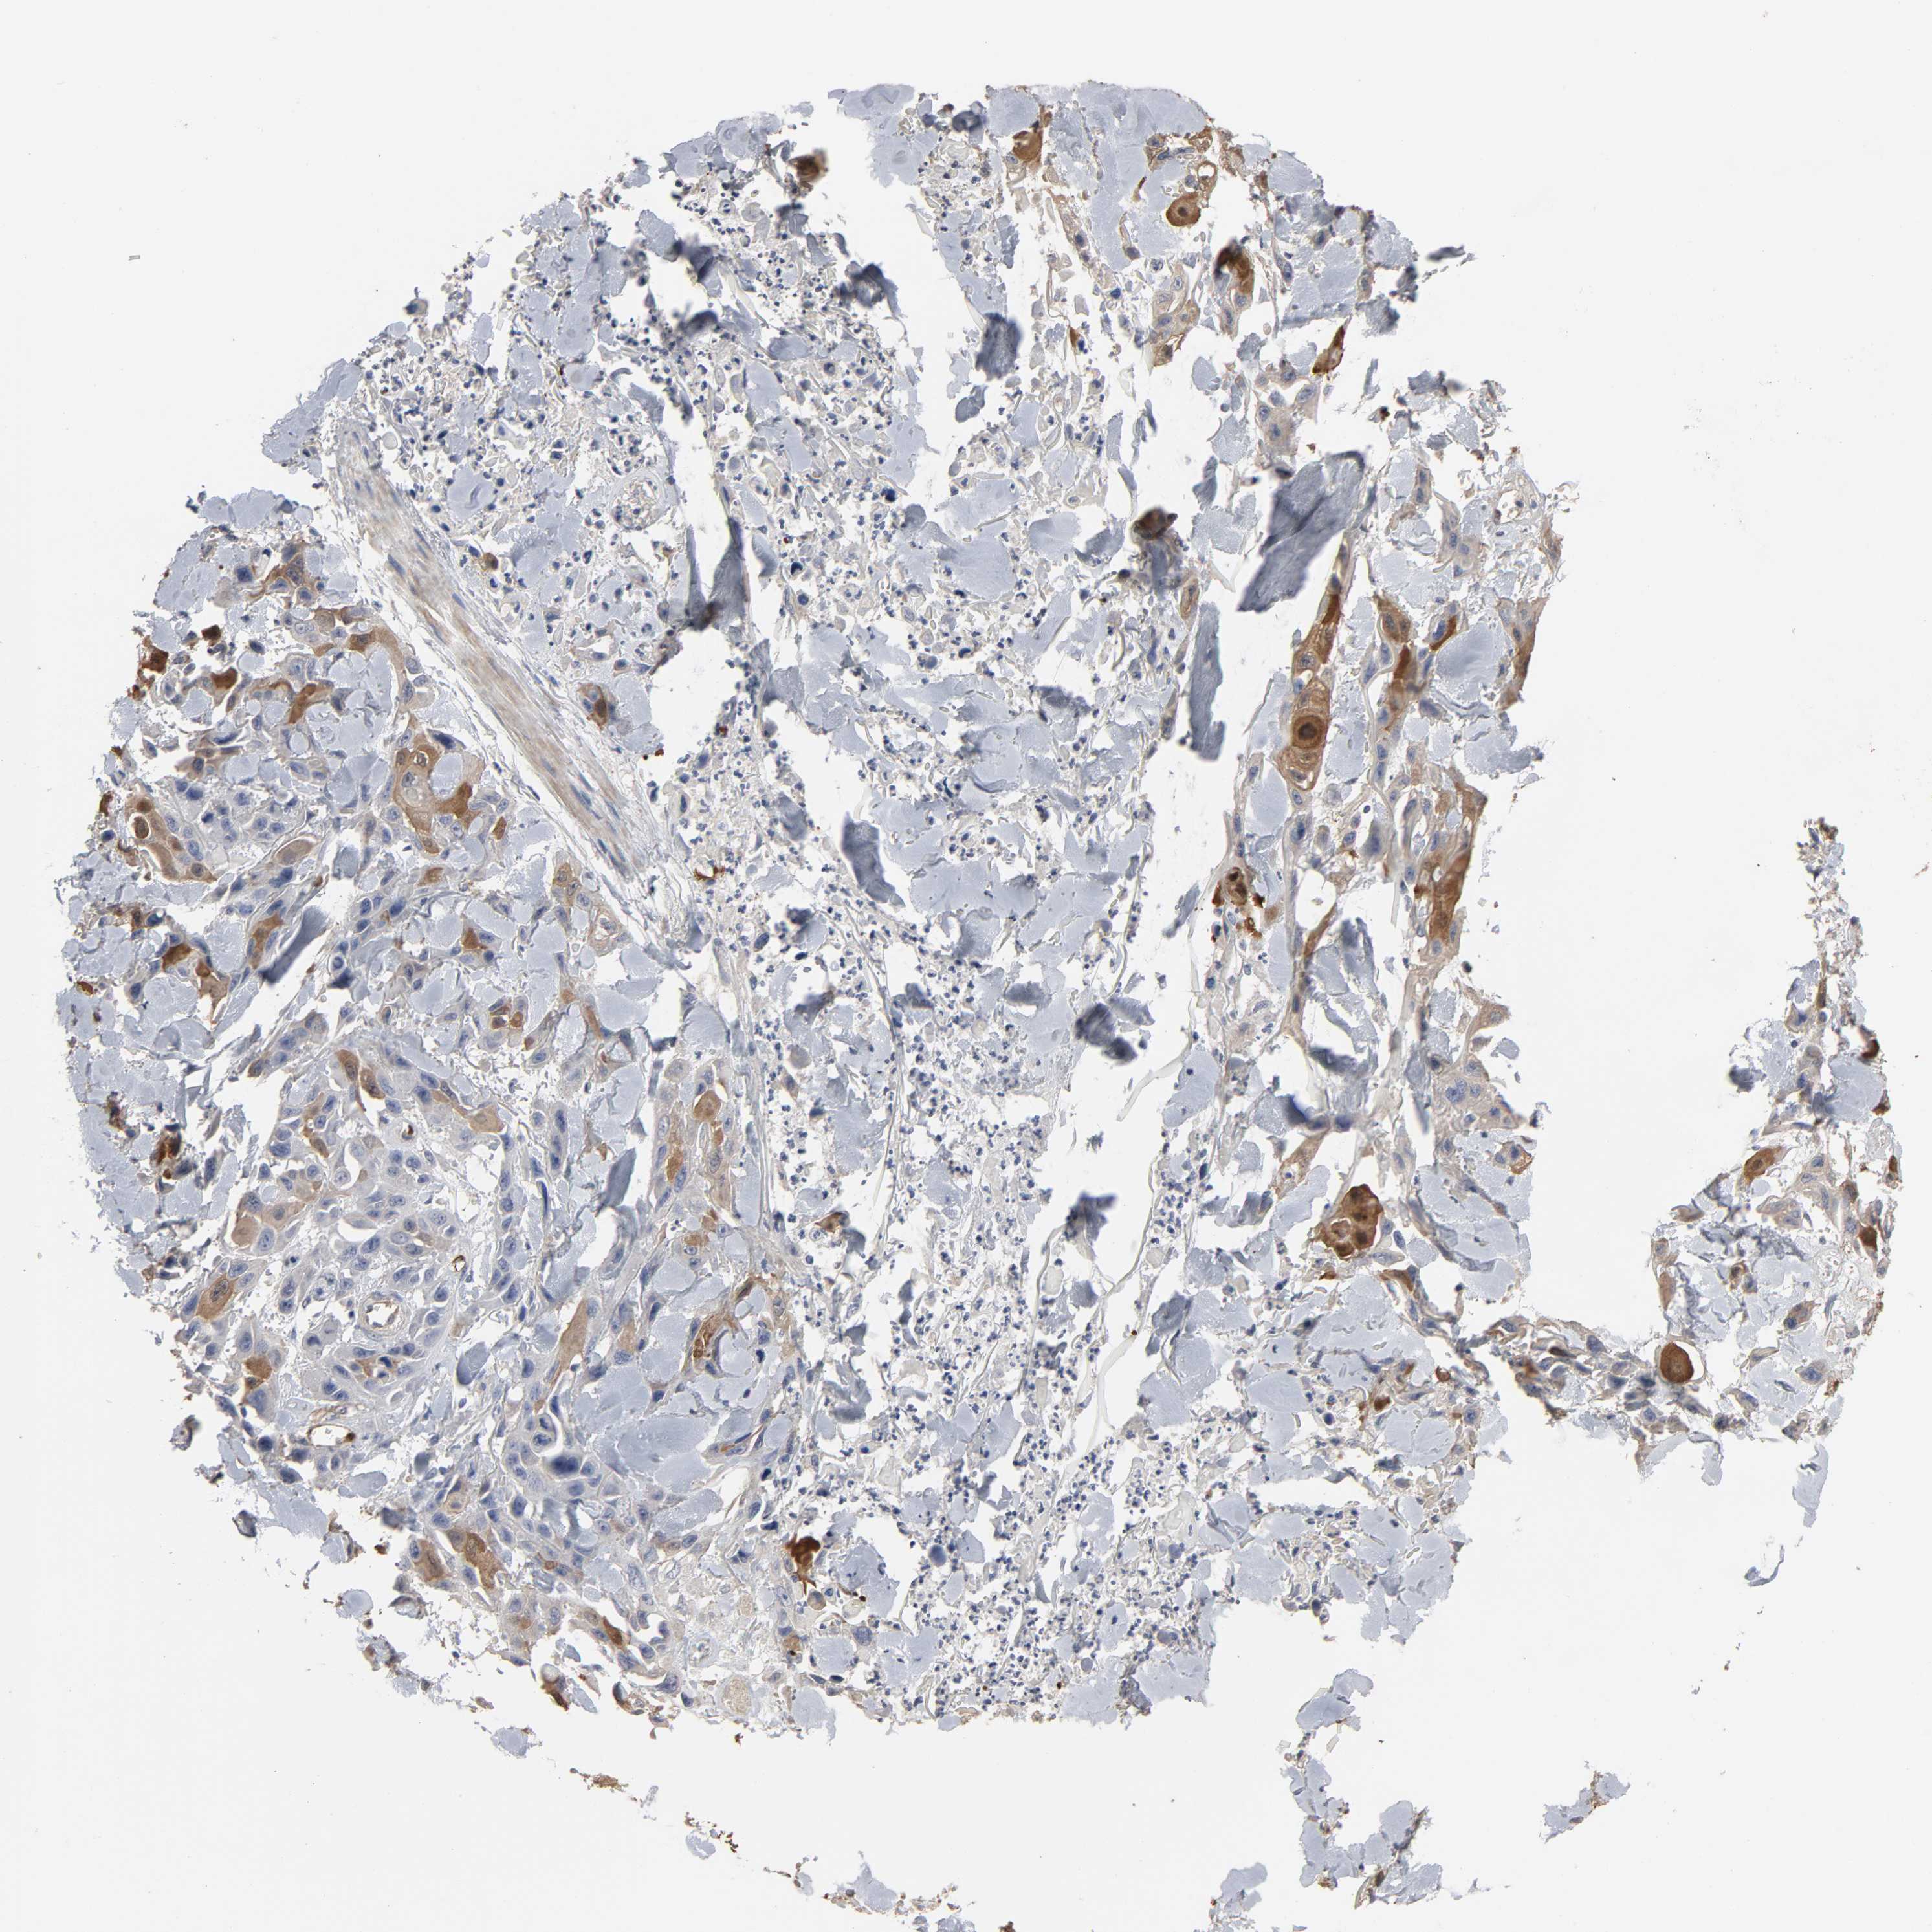

SKIN CANCER - Protein expressioni

A mouse-over function shows sample information and annotation data. Click on an image to view it in a full screen mode. Samples can be filtered based on level of antibody staining by selecting one or several of the following categories: high, medium, low and not detected. The assay and annotation is described here.

Antibody stainingi

Antibody staining in the annotated cell types in the current human tissue is reported as not detected, low, medium, or high, based on conventional immunohistochemistry profiling in selected tissues. This score is based on the combination of the staining intensity and fraction of stained cells.

Each image is clickable and will lead to virtual microscopy that enables deeper exploration of all samples and also displays staining intensity scores, fraction scores and subcellular localization as well as patient and tissue information for each sample.

Antibody CAB004028

Staining

High

Medium

Low

Not detected

Intensity

Strong

Moderate

Weak

Negative

Quantity

>75%

75%-25%

<25%

None

Location

Nuclear

Cytoplasmic/membranous

Cytoplasmic/membranous,nuclear

Squamous cell carcinoma, NOS

Basal cell carcinoma